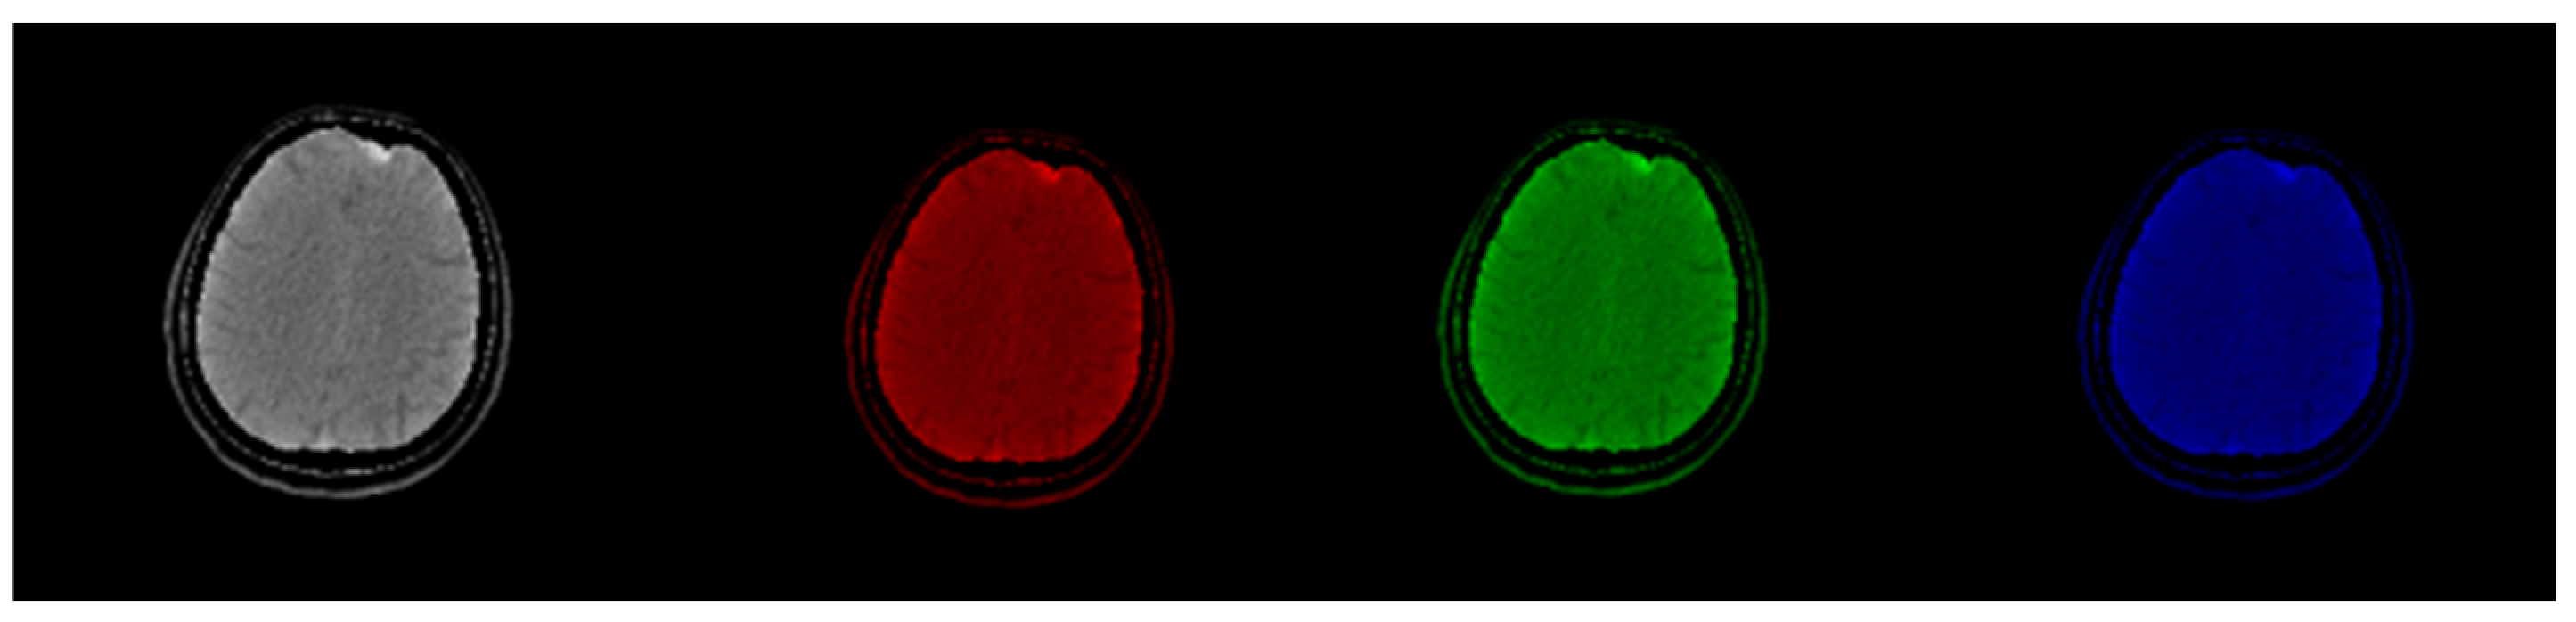

Figure 2.

Original CT slice in grayscale (left) followed by Red, Green, and Blue coloring. Gray and Green shades outperform Red and Blue in terms of the discernibility of the structures.